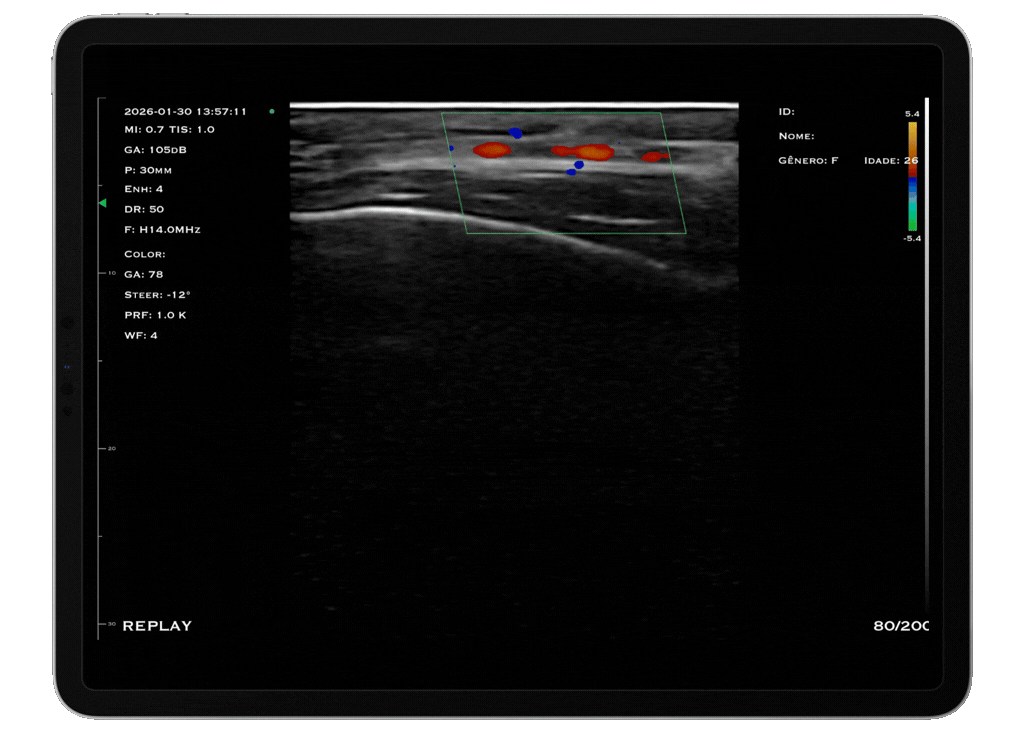

Com tecnologia linear de alta frequência (10 a 14 MHz), o modelo M4D é a escolha ideal para quem busca alta resolução em exames superficiais, com foco em detalhamento e precisão.

O trasdutor linear oferece imagens nítidas e detalhadas, permitindo a visualização precisa de estruturas como pele, tecido subcutâneo, músculos, tendões e articulações. A alta frequência garante excelente resolução para exames que exigem detalhamento extremo.

Modos: B, B/M, Color, PDI e PW

Aplicações: Visualização de articulações periféricas, avaliação de estruturas faciais, preenchedores, acesso PICC, acessos superficiais anestesia pediátrica e bloqueios periféricos.